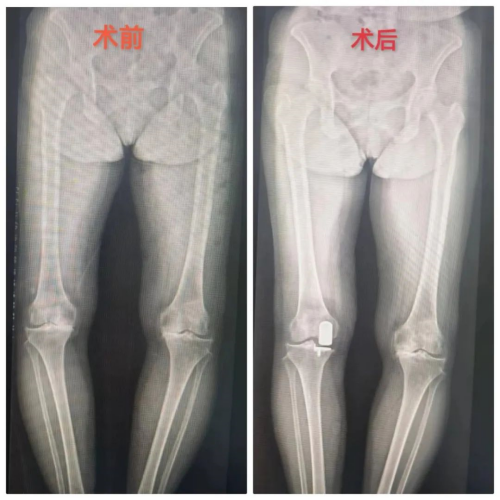

近年来,随着微创外科技术的发展和保膝理念的盛行,单髁置换术(UKA)在国内逐渐推广,我院运动医疗关节骨病科自开展膝关节单髁置换以来,为多位老年患者解决了行走之痛。4月1日上午,行“膝关节置换术”术后第二天的彭奶奶一边在病房走廊上练习行走,一边向旁边好奇的老病友介绍自己手术后的情况。

运动医疗关节骨病科主任李良军介绍:“膝关节作为人体结构最复杂的关节,又是负重关节,容易患上骨性关节炎,以往大多采用的是一刀切的全膝关节置换术,但实际上许多膝关节骨性关节炎患者只是单一间室局部病变,也就是只有一部分产生了病变。韧带结构良好,不需要全膝置换,单髁置换应运而生。所谓单髁置换,就是精准置换产生病变的部位,最大限度保留膝关节功能和本体感觉。单髁置换相比全膝置换有几大优势,主要体现在:切口小,出血量少,可以最大化地保留正常组织,术后恢复快,本体感觉好,最重要的是更具人性化。当然,如果是整个膝关节都出了问题,还是首选全膝关节置换了。”